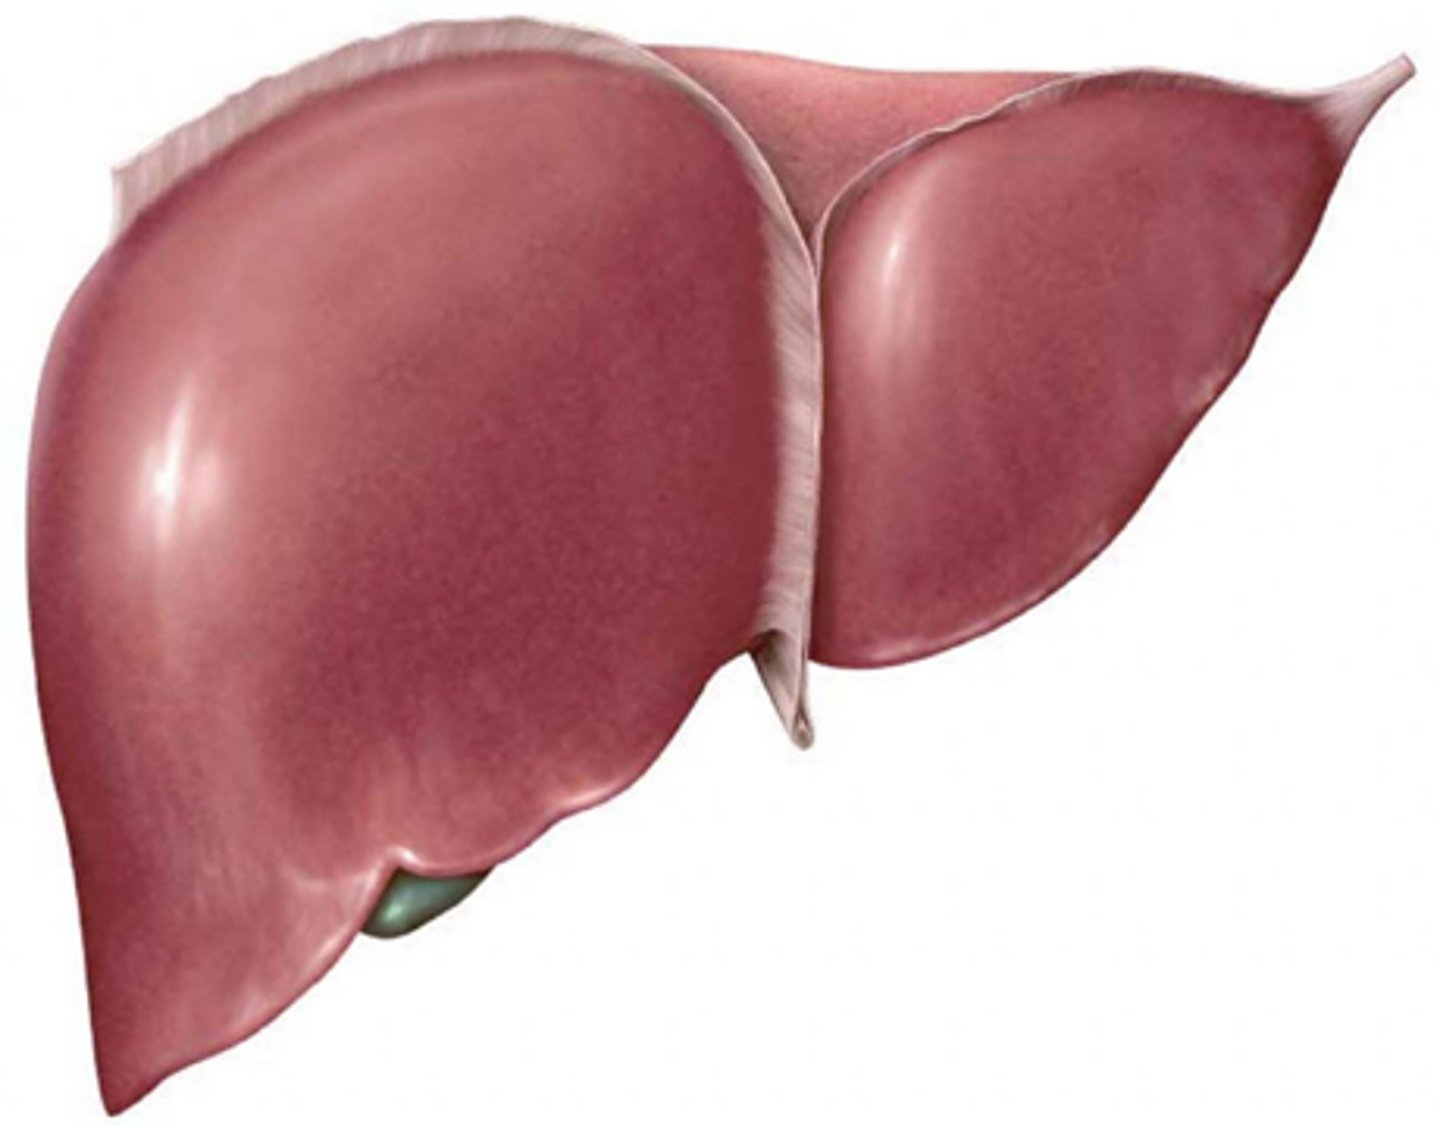

Be familiar with the anatomical position of the organs within the abdomen

Identify the lobes of the inferior portion of the liver

Identify the anterior lobes of the liver

Identify impressions on the inferior portion of the liver